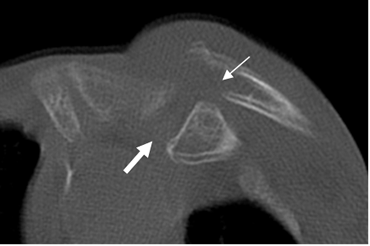

TRAUMA DE ARTICULACION ESTERNOCLAVICULAR.

Las luxaciones son de difícil detección, por lo que se necesita del TAC para hacer el diagnóstico. (1).

Las posteriores son menos frecuentes pero mas graves, por las complicaciones neurovasculares que ocasionan. (1). (Fig 56 A y B).

Fig 56A. Luxación de articulación esternoclavicular.

TAC axial. Desplazamiento posterior del tercio proximal de la clavícula, por luxación.